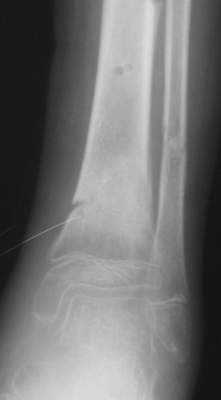

Так как речь зашла непосредственно о травме, см этапные

снимки. Как все было

Промежуточный

Нашел в комп-ре схожий случай:

1) з/репозиция, 2) фиксация 2 спицами, 3) аппарат, 4) фиксационные

спицы удалены...

См. аттачт.

А можно было наложить аппарат и по поводу ложного сустава...

По крайней мере не было бы укорочения (пусть и в 2 см)...